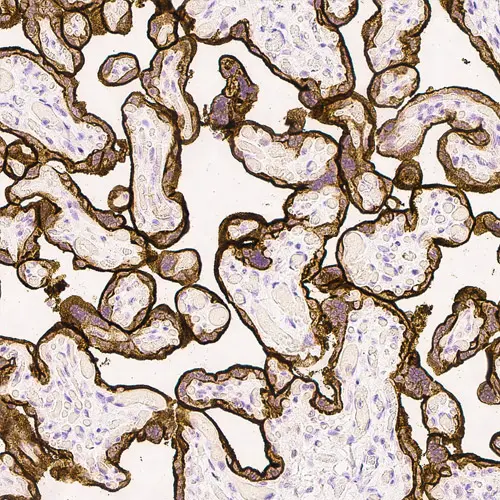

Human placenta: immunohistochemical staining for Epidermal Growth Factor Receptor. High expression of EGFR localized in the trophoblastic layer of the placental villi. Epidermal Growth Factor Receptor: clone EGFR.113

El clon EGFR.25 se eleva hasta el dominio citoplasmático de la molécula de EGFR, mientras que el clon EGFR.113 se eleva hasta el dominio extracelular.